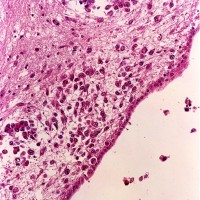

悪性黒色腫(melanoma) の細胞で,多核の細胞や,細胞の大小不同,核の異型性が目立ち悪性腫瘍の所見です。右の画像では大小の血管が腫瘍組織の間に発達しています。非常に血管に富む腫瘍です。